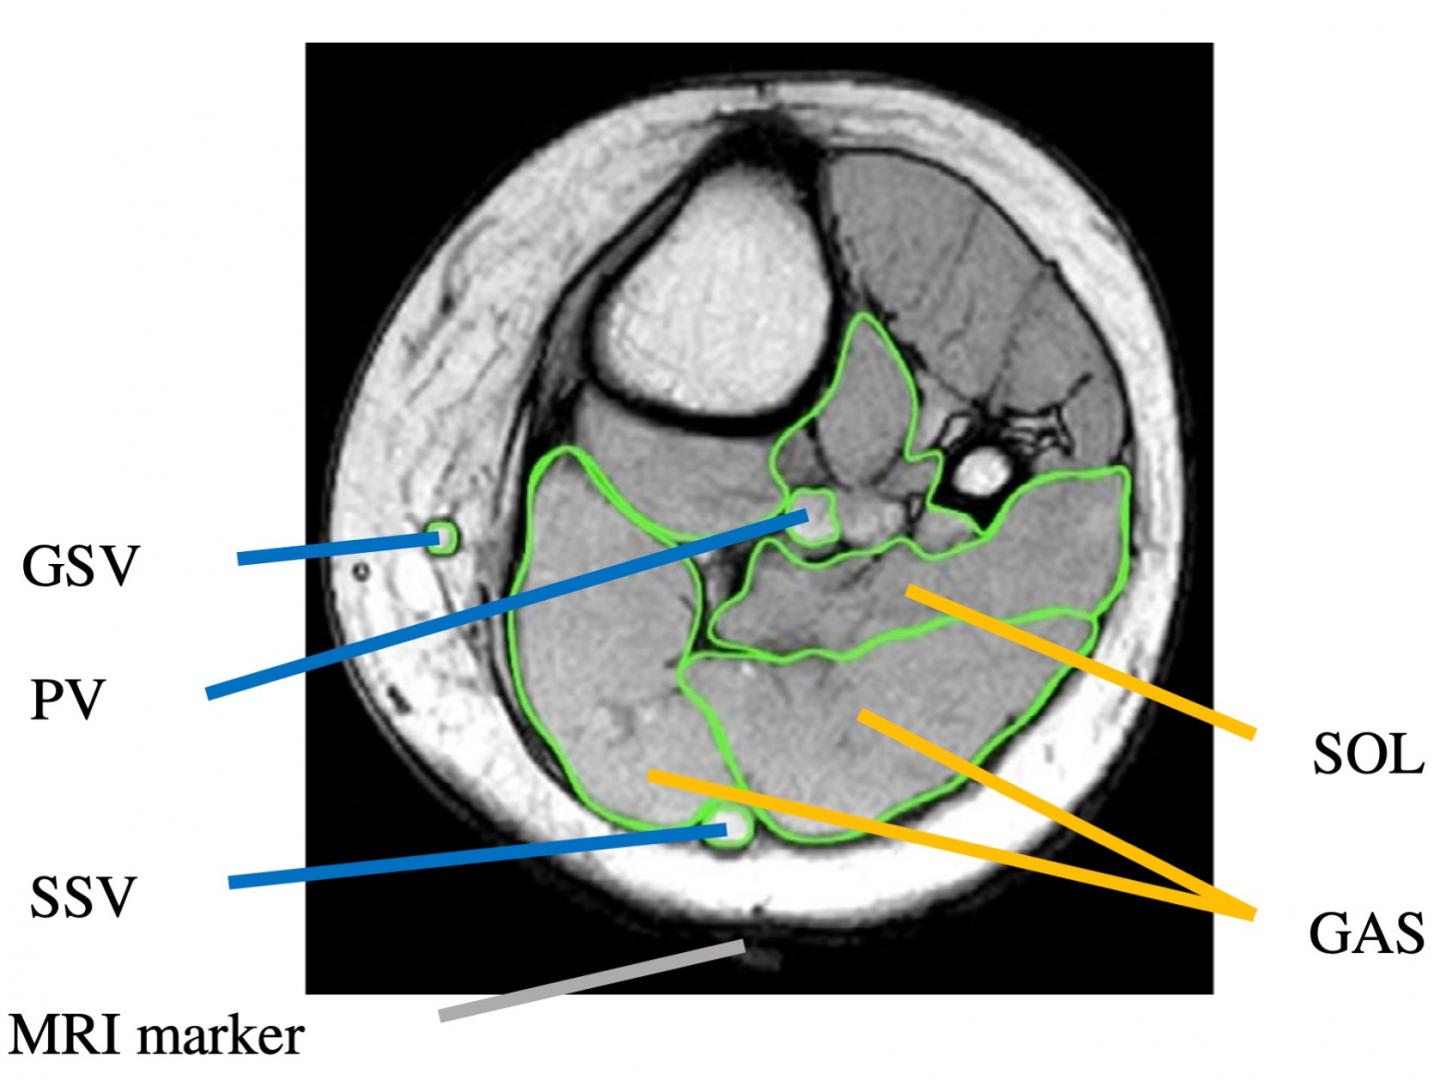

image: T1WI with muscle and vein ROI set on the T1WI of the cross section at the center of the marker. Muscle area was measured for GAS and SOL. The vein area was measured for the PV and the GSV and SSV. PV, popliteal vein;

GAS, gastrocnemius muscle; SOL, soleus muscle; GSV, great saphenous vein; SSV, small saphenous vein.